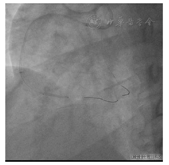

2022年6月21日行RCA-CTO介入治疗,双桡动脉穿刺,左侧桡动脉植入6F动脉鞘管,右侧桡动脉植入7F动脉薄壁鞘管,经左侧桡动脉鞘送入6F EBU 4.0至左冠状动脉开口,经右侧桡动脉鞘送入7 F SAL 1.5至右冠状动脉开口,双侧造影显示RCA-CTO近段及远端血管床及侧支循环(图5)。

经前向指引导管(7 F SAL1.5)操控Finecross130微导管及XT-R导丝不能前向进入RCA远段,更换指引导丝XT-A、Gaia Second、Pilot 150仍不能前向进入RCA远段,对侧造影显示与远段血管床偏离(图6)。